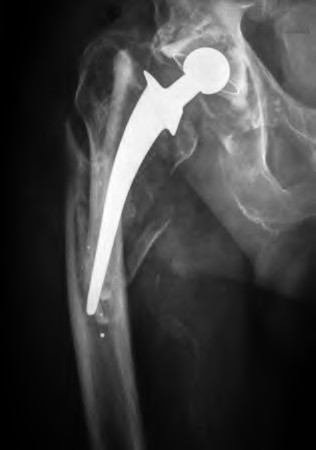

The radiograph demonstrates a periprosthetic femur fracture extending to the tip of the stem. The long spiral fracture is consistent with a loose implant. The bone stock is sufficient. Therefore, this fracture pattern would classify as a B2 using the Vancouver classification system. The Vancouver classification for periprosthetic femoral fractures is simple yet incorporates all the pertinent factors such a location, stem fixation, and bone stock. Type A is a trochanteric fracture- lesser or greater. These can be treated non-operatively usually and ORIF if symptomatic. Type B fractures are around or just below the stem and are subdivided into three types. Type B1 is a fracture with a well fixed stem.

The treatment is cable plating or allograft struts or a combination of the two. Type B2 is a fracture with a loose stem with good bone stock. The treatment is a cementless porous coated long stem atleast two diameter length past the

fracture site. Type B3 is a fracture with a loose stem and comminution. For younger patients, use cementless porous coated long stems with allograft struts. For older patients, consider a tumor prosthesis. Cement fixation is sometimes necessary Type C is a fracture well below the stem tip. These can be treated independently of the prosthesis.

A 72-year-old male presents 2 years status post fixation of an impending pathologic right femur fracture due to metastatic renal cell carcinoma. He is minimally ambulatory due to pain. Despite radiation therapy, there has been progression of the lesion with extensive cortical bone loss, which is shown in Figure A. A proximal femoral replacement arthroplasty is performed without complications, and is demonstrated in Figure B. Which of the following is true regarding this patients post-operative course?

Deep prosthetic infection is the most common complication after hip arthroplasty performed for salvage of failed internal fixation after pathologic proximal femoral fracture secondary to malignancy.

Jacofsky et al reviewed the complications in 42 patients with a mean age of 63 who were treated with hip arthroplasty for salvage of failed treatment of a pathologic proximal femoral fracture. Multiple different constructs were used.

The most common complication was deep prosthetic infection, which occurred in nearly 10% of the patients studied. All infections occured in patients whom had previously received radiation. The mean Harris Hip score improved from 42 to 83 points post-operatively, and 41 of the 42 patients were ambulatory at follow-up. Implant survivorship free of revision for any reason at 5 years was 90%, and free of revision for aseptic failure or radiographic failure was 97%.

Figure A shows a lytic lesion of the proximal femur with an intramedullary implant. Figure B shows a proximal femoral replacement.